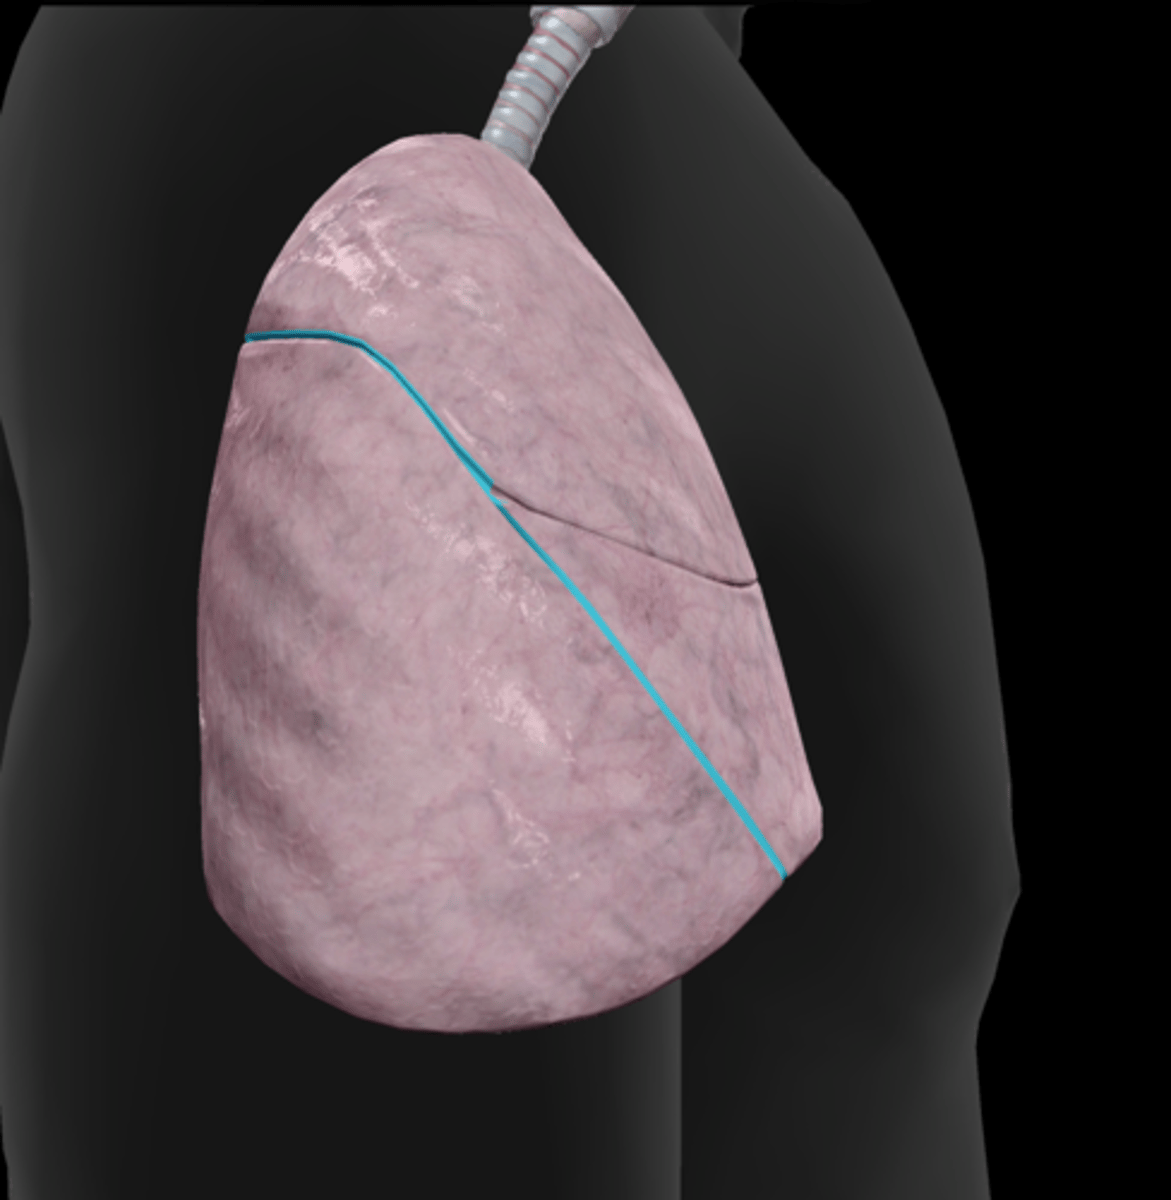

Superior lobe

Middle lobe

Inferior lobe

Horizontal fissure

Oblique fissure